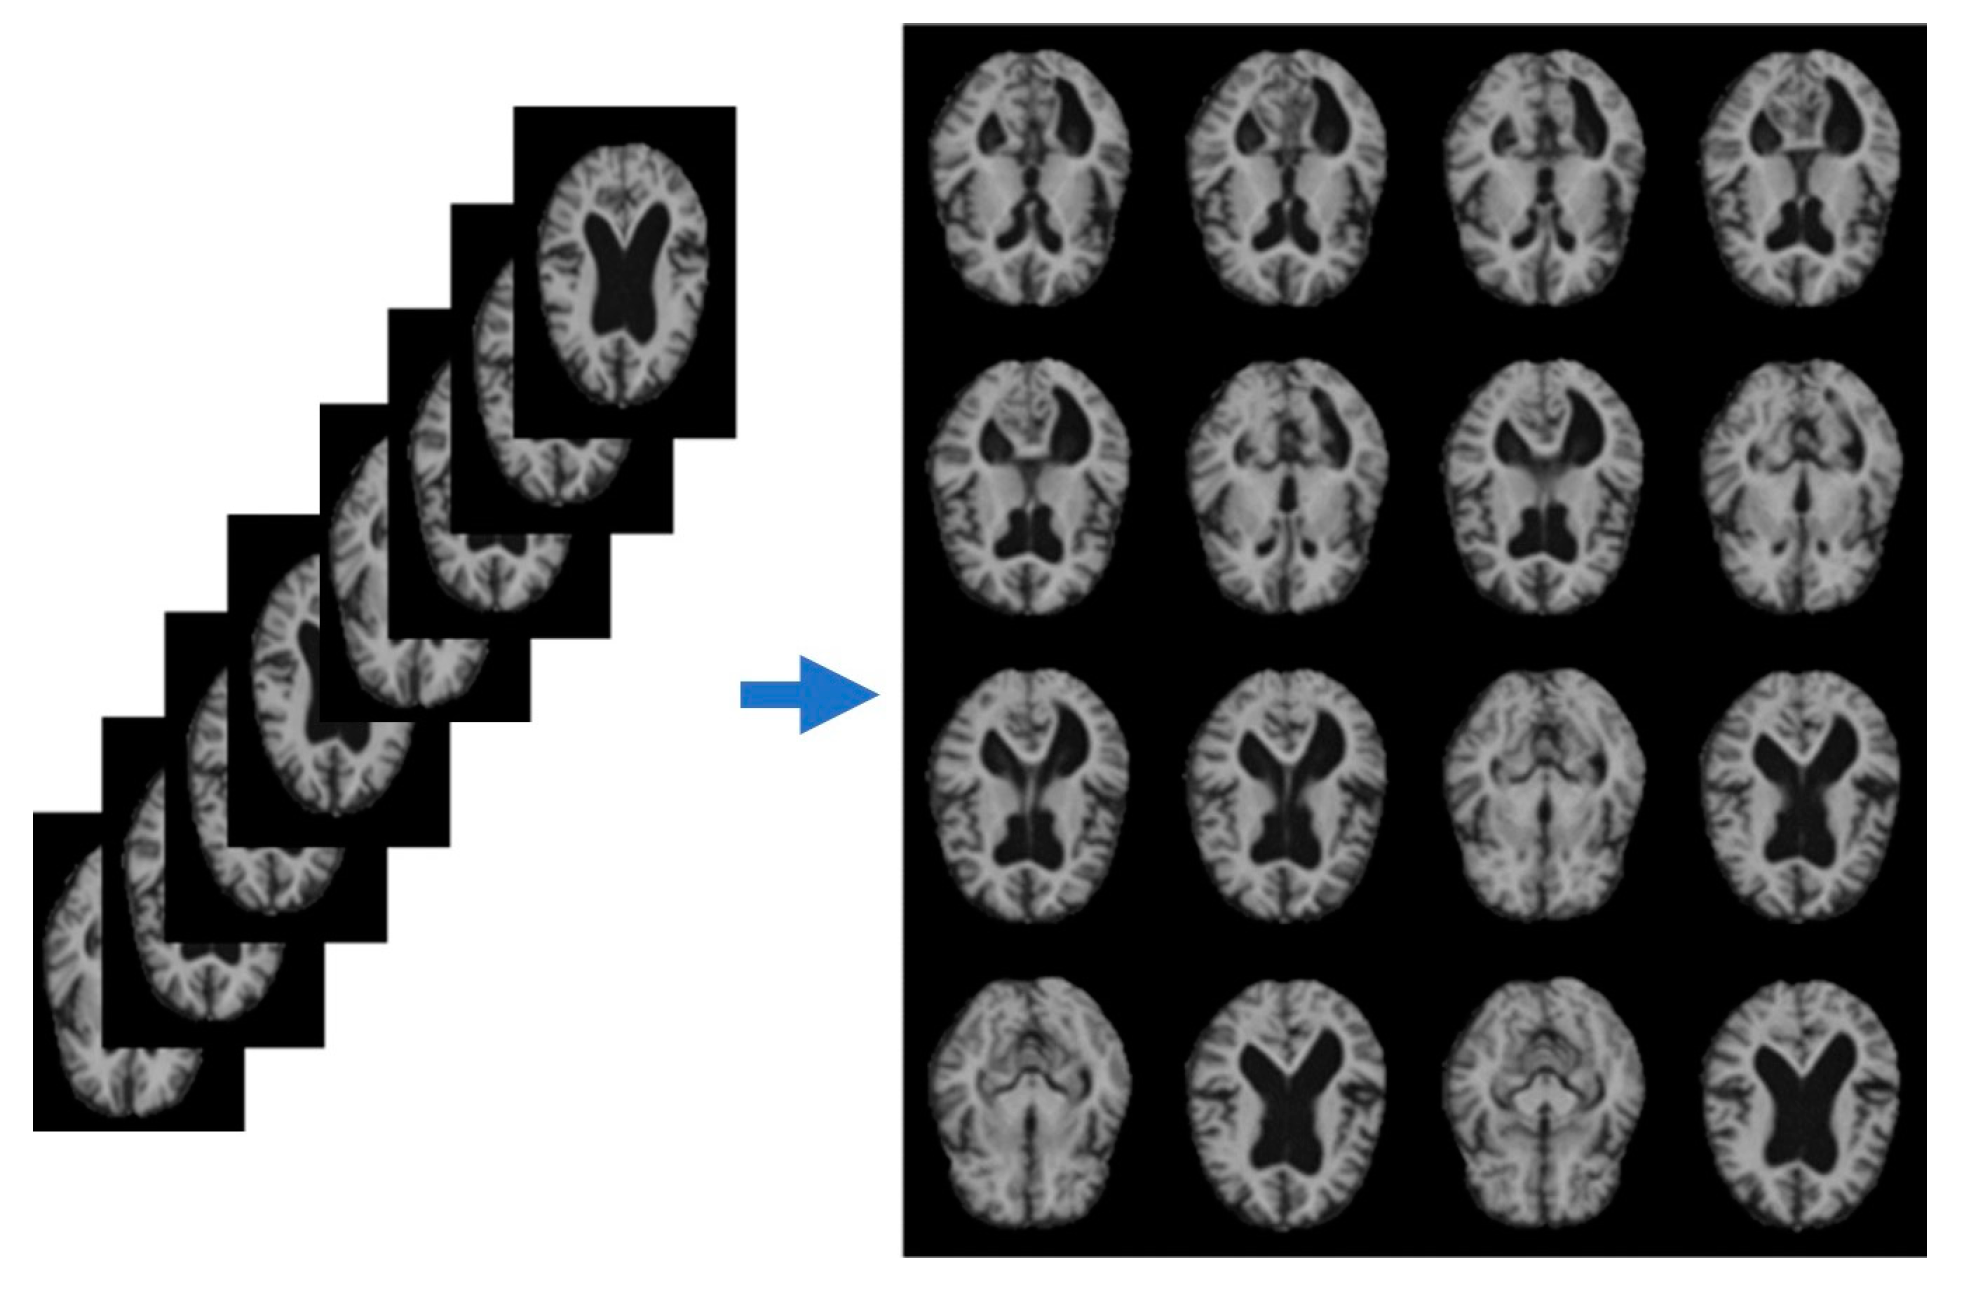

Entropy-based slicing extracts relevant features from the pre-processed MRI data. This technique partitions the brain volume into smaller regions based on voxel intensity distribution, identifying areas of high entropy associated with structural abnormalities or tissue degeneration. The algorithm computes voxel intensity entropy across multiple slices, selecting regions with the highest entropy values for further analysis. We extracted the 16 most informative slices and arranged them in a 4 × 4 grid, as shown in Figure 2.

Figure 2. Pre-processed image after applying entropy slicing.